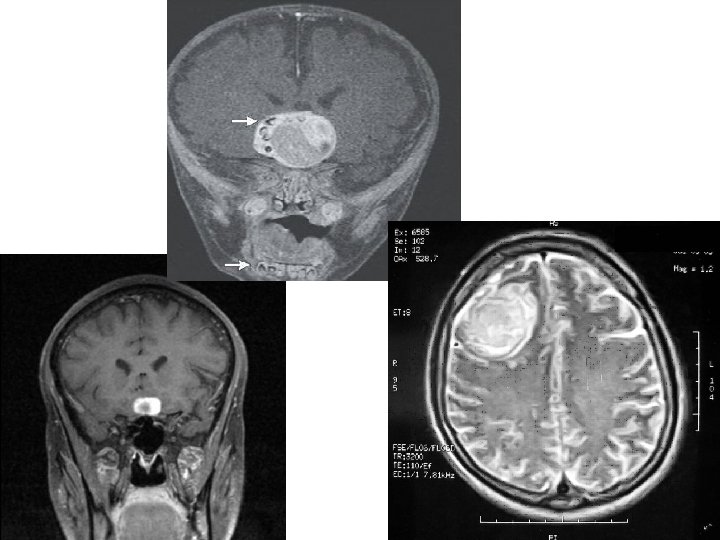

Okcipitální kraniotomie • Okcipitální lalok, pineální krajina (po tentoriu, podél falxu) • v. magna Galeni, fornix, corpus callosum • 3. komora, krvácení do komory